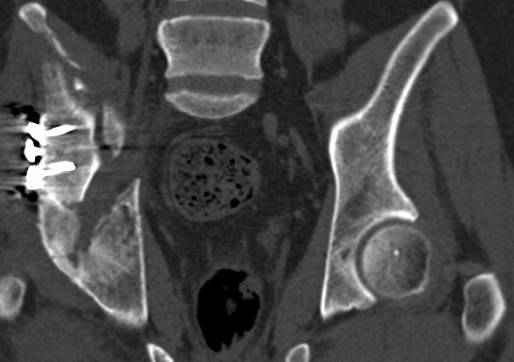

Интересно было бы посмотреть рентгенограммы до операции. У меня впечатление, что я не все вижу, что тут есть... Уважаемые Господа "тазисты" и "тазологи", к какому типу переломов вертлужной впадины по Летурнелю вы бы отнесли это случай?

Из переломов проходящих через крыло и/или заднюю стенку ни простой перелом "передней колонны" (явно имеется пером задней стенки, и не видно перелома седалищной или лонной), ни простой "поперечный", ни ассоциированный "Т-образный" (т.к есть перелом крыла и не видно перелома седалишной), ни ассоциированный "задняя колонна+задняя стенка", на ассоциированный "поперечный+задняя стенка", ни ассоциированный "передняя колонна+задняя гемисфера" (не видно перелома седалищной), ни ассоциированный "обе колонны" (не видно перелома лонной седалищной) не подходят под эту классификацию....

к таковым себя не причисляю, но...обычное дело для нашей страны - выкладывать 3D и не показывать стандартные проекции Judet. Дигност представляет те ракурсы, которые по-его мнению наиболее информативны, более того комп сам достраивает какие-то мелкие повреждения по 3D по своему усмотрению. По данной реконструкции можно предполагать высокий двухколонный перелом с оскольчатыми передней и задней колоннами, оскольчатую высокую переднюю колонну с задним полупоперечником или одно из перечисленных с вовлечение КПС. У меня впечатление за второй вариант, но нужно обследовать нормально - проекции, сканы.

высылаю дополнительно сканы.